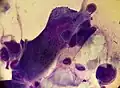

![]() A positive Tzanck test, showing three multinucleated giant cells ("Tzanck cells") in center. | |